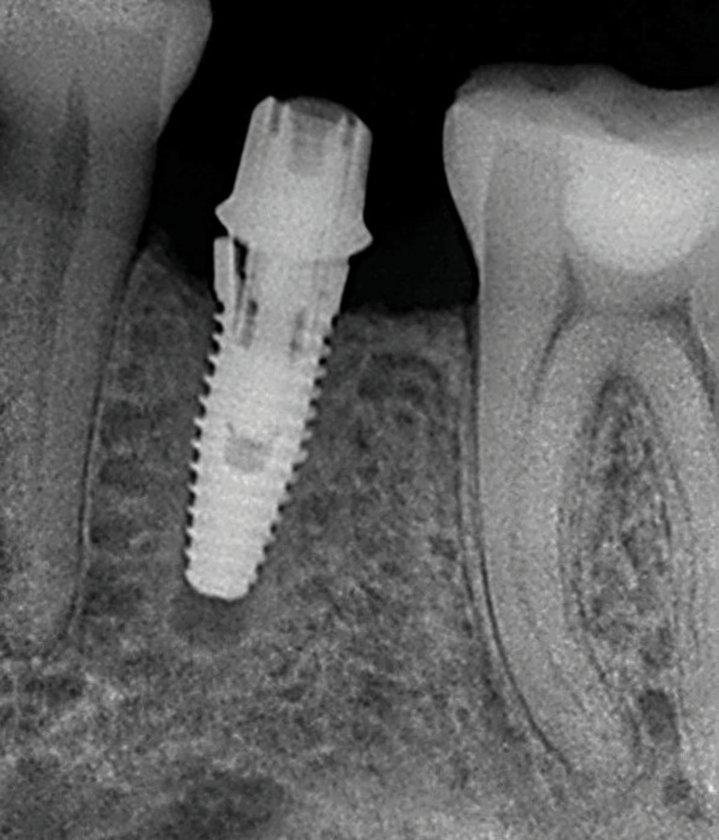

Implants with internal hex connections are more prone to failure at the connection than those with external hex connections.28 This is related to the thickness of the metal at the thinnest point between the internal surface of the interface and the external surface at the crestal area of the implant. When overloaded, implants with an internal hex connection may present with fractures at the points of the hex.29 These points are where the metal is the thinnest at the crestal portion of the implant and where stress is concentrated during overloading. This is less problematic in wider diameter implants because the metal is thicker in this area of the implant; however, in standard or narrow diameter implants, fracture may result, causing catastrophic failure of the implant (Figure 1). This may also occur in other internal implant connection types, such as trilobe connections, especially when the crestal thickness of the implant is minimal, leading to fracture of the coronal aspect of the implant (Figure 2). Implants with conical connections are not immune to potential fracture in this area, and the thin walls of some standard or narrow diameter models may split even without the isolated stress points observed in internal hex-, trilobe-, and octagon-type connections (Figure 3).30 Sometimes, fractures of implants at the coronal aspect are not clinically visible but, instead, are identified radiographically either after a patient complaint of pain in the area, due to the presence of soft-tissue inflammation, or during a routine examination with no patient complaint (Figure 4).

Coronal implant fracture, whether it is incomplete (Figure 5) or involves a visible loss of a portion of the implant platform (Figure 6 and Figure 7), results in catastrophic failure of the implant. The presence of any fracture in the coronal aspect of an implant necessitates explantation. These implants cannot be salvaged because an incomplete fracture will continue to propagate due to micromovement of the abutment and implant at the connection during function. Off-axis loads are amplified when there is a longer distance between the implant's platform and the most coronal surface of the restoration because the fulcrum arm is increased, allowing higher loading forces at the platform.31

(4.) A failed implant that underwent mechanical overloading leading to fracture of the coronal portion adjacent to the implant-abutment connection.

Figure 4